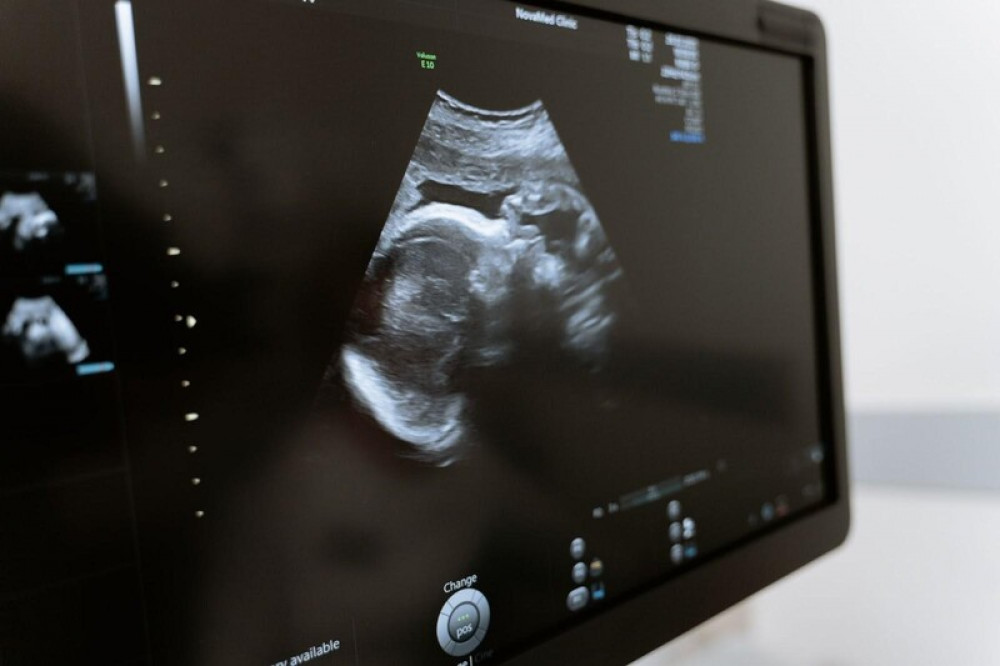

Ultrasonografi (USG) fetomaternal (atau sering disebut ultrasonografi skrining anatomi janin) merupakan salah satu pemeriksaan untuk kehamilan tertentu. Pemeriksaan ini membantu Ibu untuk mengetahui kondisi janin di dalam perut secara detail, seperti ada tidaknya kelainan pada janin. Dengan begitu, Ibu dapat mengenali risiko kesehatan bagi Ibu dan bayi serta meminimalisirnya sejak dini.

Ultrasonografi fetomaternal merupakan metode pemeriksaan untuk mengetahui gambaran real-time dari janin secara detail, untuk memperoleh informasi tentang kelainan pada janin.

Menurut SynappseHealth, pemeriksaan tersebut dilakukan dengan menghasilkan gambaran dari jaringan, menggunakan gelombang ultrasonik dengan frekuensi tinggi (Megahertz). Gelombang tersebut dipancarkan ke tubuh melalui suatu alat transducer, lalu memantul saat berada di perbatasan antara jaringan dan tulang atau antara jaringan lunak dan cairan. Pantulan tersebut direkam dan dianalisis oleh dokter, sehingga dokter dapat mengetahui bentuk dan ukuran organ tubuh janin dalam rahim.

Melalui pemeriksaan ini, aliran darah pada tali pusar serta aliran pada pembuluh darah rahim dan otak pun dapat diketahui. Tak hanya itu, dokter juga bisa melakukan observasi pada bagian-bagian tubuh bayi, seperti otak dan jantung.

5. Gambaran hasil pemeriksaan akan tampil secara real time di layar monitor yang terhubung dengan transducer.